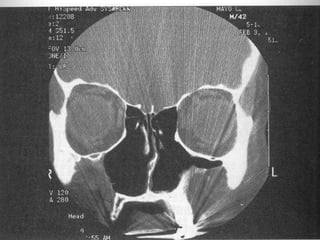

Radiographic Findings

1. Mucoperiosteal thickening of the paranasal sinuses.

2. Loss of definition of the OMC secondary to resorption of the ethmoid bulla and

uncinate process.

3. Hypoplasia of the maxillary sinuses.

4. Enlargement of the nasal cavities with erosion and bowing of the lateral nasal

wall.

5. Bony resorption and mucosal atrophy of the inferior and middle turbinates.

Radiographic Findings 1. Mucoperiostealthickening of the paranasal sinuses. 2. Loss of definition of the OMC secondary to resorption of the ethmoid bulla and uncinate process. 3. Hypoplasia of the maxillary sinuses. 4. Enlargement of the nasal cavities with erosion and bowing of the lateral nasal wall. 5. Bony resorption and mucosal atrophy of the inferior and middle turbinates.